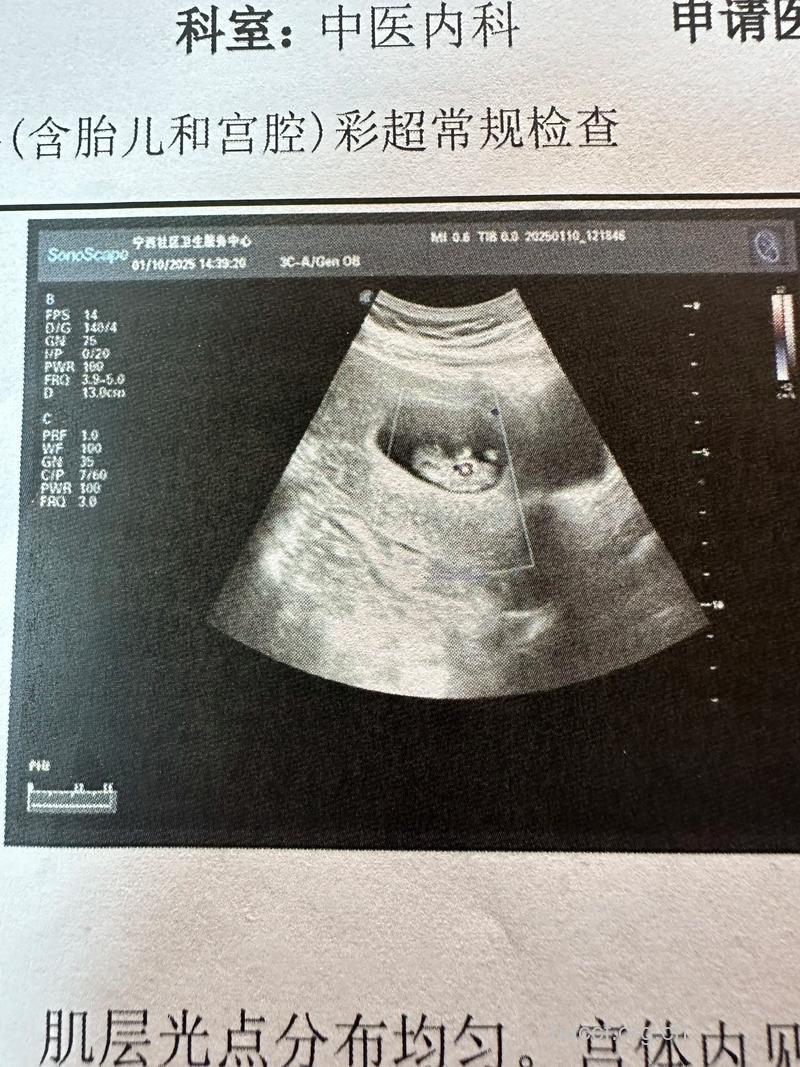

胎儿第三十三周的发育情况胎体丰满,毳毛脱落。